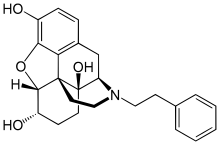

Opium alkaloids and derivatives

Phenanthrenes naturally occurring in (opium):